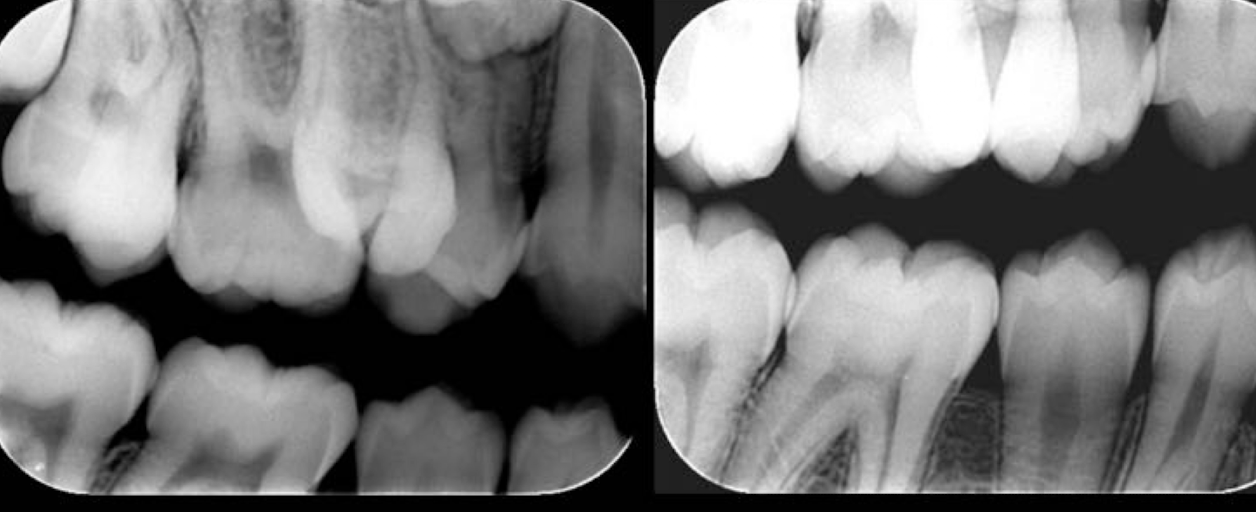

Based on this xray, what developmental and congenital abnormality is observed?

a. number of teeth

b. size of teeth

c. eruption of teeth

d. morphology of teeth